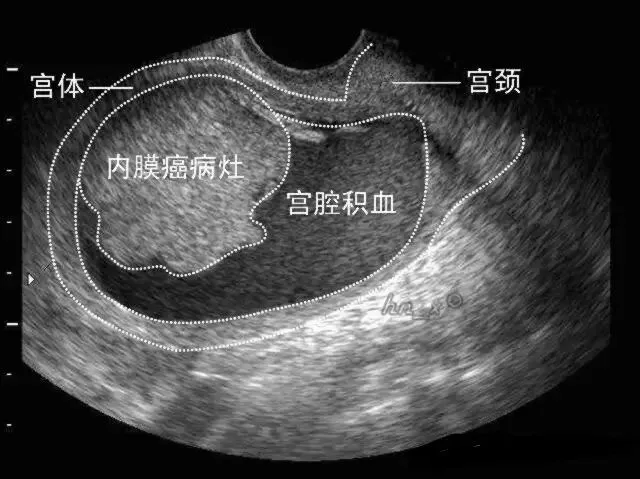

●二维超声表现:子宫内膜增厚、当病变累及肌层时局部内膜与肌层界限不清、早期子宫外形轮廓多无明显改变。

局灶性子宫内膜癌宫腔积血声像